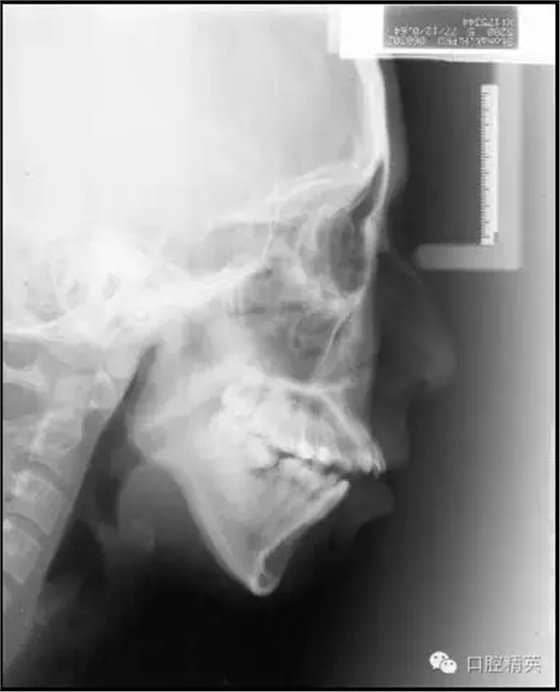

自上個(gè)世紀(jì)末開始至今,微螺釘種植體支抗在正畸領(lǐng)域的應(yīng)用已有近20年的歷史。而隨著其被越來越廣泛靈活地應(yīng)用于正畸臨床工作中,其在垂直向上的獨(dú)特優(yōu)勢(shì)也越來越突出,大致可以歸納為以下六個(gè)方面:高角病例全方位垂直向控制;改善露齦微笑——壓低上前牙;打開重度深覆合——壓低下前牙或同時(shí)壓低上前牙;矯正平面傾斜——壓低一側(cè)牙齒;壓低過萌長(zhǎng)磨牙——壓低磨牙;直立近中傾斜的磨牙——直立并壓低磨牙。本文將以結(jié)合典型病例的方式對(duì)以上六種微螺釘種植體支抗在垂直向上的應(yīng)用一一論述說明。

高角病例全方位垂直向控制的概念主要涵蓋了兩個(gè)方面,即針對(duì)磨牙的后部垂直向控制和針對(duì)上前牙的前部垂直向控制。

后部垂直向控制是基于高角骨面型的形成機(jī)制提出的。研究指出,高角骨面型的形成主要是由于相對(duì)較小的髁突垂直生長(zhǎng)量,和相對(duì)較大的上頜骨垂直生長(zhǎng)量及上下頜后牙牙槽突垂直生長(zhǎng)量,所共同導(dǎo)致的下頜骨后下旋轉(zhuǎn)所致。

簡(jiǎn)言之,即髁突與磨牙區(qū)的垂直生長(zhǎng)量失衡。對(duì)這類患者,即使是正處于生長(zhǎng)發(fā)育期者,我們也很難寄希望于其髁突的生長(zhǎng)在正畸治療中或治療后能自動(dòng)超過磨牙區(qū)的垂直生長(zhǎng),進(jìn)而控制住其下頜平面,因?yàn)橥ǔ;颊咴瓉淼腟N-MP角越大,下頜平面隨生長(zhǎng)發(fā)育會(huì)變得越陡。

因此,如果依賴髁突的自然生長(zhǎng),阻止其在正畸治療中因不可避免的磨牙升高而發(fā)生后下旋轉(zhuǎn)是很困難的,更不必說前上旋轉(zhuǎn)下頜平面。

既然我們很難改變患者髁突生長(zhǎng)不足的問題,就只好從控制其上頜骨及磨牙區(qū)的垂直生長(zhǎng)著手了,由于抑制生長(zhǎng)本非易事,控制患者的磨牙高度就成了控制其下頜平面最切實(shí)可行的手段。而通過壓低磨牙來控制高角患者的下頜平面,乃至實(shí)現(xiàn)其下頜平面的前上旋轉(zhuǎn)正是后部垂直向控制的概念及意義所在(圖1)。

前部垂直向控制則是指控制上前牙向上向后移動(dòng)。 這一概念源于Tweed-Merrifield技術(shù)的方向性力系統(tǒng)。這一技術(shù)一直被認(rèn)為能夠?yàn)棰蝾惛呓腔颊邘碜罴训某C治效果,技術(shù)標(biāo)志之一就是著名的方向性力系統(tǒng),即通過控制患者的下后牙和上前牙來控制其下頜平面和合平面,實(shí)現(xiàn)這一控制的所有力的合力矢量均需向上向前,所需方向性力由牽引皮圈和可調(diào)整方向的J鉤頭帽提供。最終實(shí)現(xiàn)下切牙直立于基骨之上,上前牙向上向后移動(dòng),為下頜骨的前上旋轉(zhuǎn)創(chuàng)造條件,而這也正是前部垂直向控制的概念及意義所在(圖2)。

在這一全方位垂直向控制的理念中我們需要明確,后部垂直向控制,不論是磨牙的絕對(duì)壓低還是相對(duì)壓低(向遠(yuǎn)中直立或阻止其伸長(zhǎng))均是實(shí)現(xiàn)下頜平面前上旋轉(zhuǎn)的必要條件;而后上移動(dòng)上前牙的前部垂直向控制則是重要條件。關(guān)于這一點(diǎn)我們將在對(duì)四大類高角病例的典型案例所進(jìn)行的垂直向控制的分析中反復(fù)論述和強(qiáng)調(diào)。

四大類高角病例為: 前牙開合,無露齦微笑; 前牙深覆合,無露齦微笑; 前牙深覆合,露齦微笑;前牙開合,露齦微笑。今天我們先來看一下,前牙開合,無露齦微笑高角病例的全方位垂直向控制。

Ⅰ類或Ⅱ類高角,前牙開合,但前牙垂直向唇齒關(guān)系正常,即沒有露齦微笑。這類高角病例將最直接而有效地發(fā)揮微螺釘種植體支抗在垂直向上的優(yōu)勢(shì)。在后部,應(yīng)用微螺釘進(jìn)行后部垂直向控制,壓低后牙,解除支點(diǎn),下頜平面前上旋轉(zhuǎn),前牙開合關(guān)閉。在前部,因?yàn)闆]有露齦微笑的問題,上前牙并不需要實(shí)現(xiàn)絕對(duì)壓低,僅需保持住其垂直向位置,阻止因上前牙的伸長(zhǎng)而導(dǎo)致下頜平面前上旋轉(zhuǎn)的空間減小。

因此,即使對(duì)于拔牙病例因鐘擺效應(yīng)上前牙有伸長(zhǎng)趨勢(shì),通過直絲弓矯治技術(shù)中的搖椅弓也能夠很好地實(shí)現(xiàn)前部的垂直向控制。這類高角患者的全方位垂直向控制充分說明,后部垂直向控制,即磨牙的絕對(duì)壓低或相對(duì)壓低(向遠(yuǎn)中直立或阻止其伸長(zhǎng))是實(shí)現(xiàn)下頜平面前上旋轉(zhuǎn)的必要條件,而后上移動(dòng)上前牙的前部垂直向控制并不是必需的,僅需控制即可,甚至上前牙稍有伸長(zhǎng),因?yàn)闆]有露齦微笑,只要下頜平面可以前上旋轉(zhuǎn)到一個(gè)理想的位置,頦部位置和形態(tài)得到顯著的改善,也是完全可以接受的。